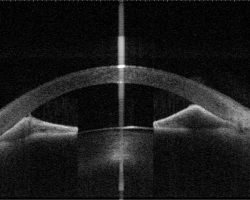

An eye with peripheral anterior synechia (PAS) captured by anterior-segment swept-source OCT. Image courtesy of Prof Clement Tham from Department of Ophthalmology and Visual Sciences, The Chinese University of Hong Kong.